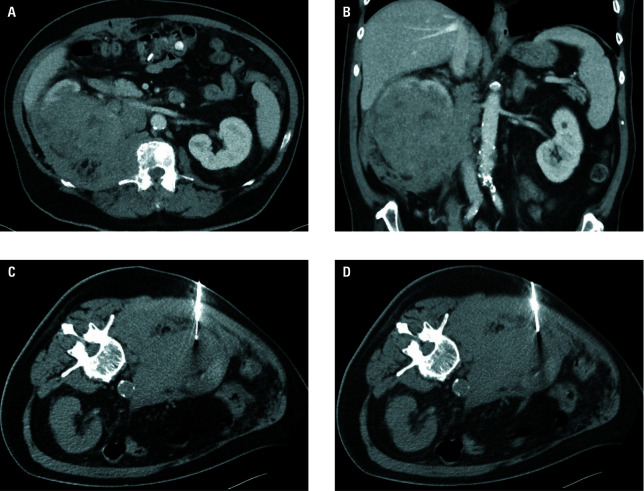

Materials and methods: A total of 138 percutaneous biopsies for tumors ranging from 21 to 133 mm in diameter (median, 72 mm) were carried out in 134 patients with suspected mRCC over a 5‑year period. The biopsy location was variable, with kidney biopsy performed in 77 cases (55.8%), and other localizations (retroperitoneum, peritoneal cavity, liver, pelvis, pleural space, lung, mediastinum, chest or abdominal wall, and pancreas) in 61 cases (44.2%).

Results: As many as 288 biopsies (97.1%), yielded truepositive results, and 4 procedures (2.9%) yielded histologically falsenegative results that required confirmation through extended rebiopsy. RCC was the most common individual diagnosis (85.5%), with non‑RCC histology verified in 14.5% of cases. In total, 32 complications (23.2%) were confirmed, 2 of which were pneumothoraces, 29 were minor bleeding that needed only conservative management, and 1 case required angiography and embolization for hemorrhage treatment. While no significant relationship between the biopsy success and lesion localization (renal vs other) was found (P = 0.13), the relationship between complication rate and biopsy localization (renal vs other) was significant (P = 0.01).

Abstract Image